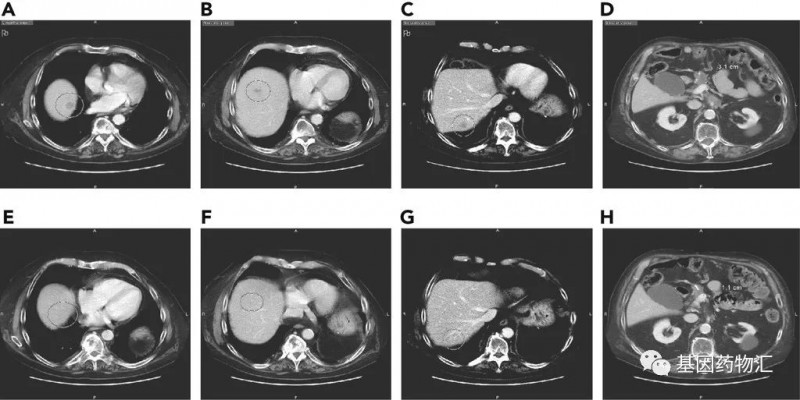

Sotorasib对于一部分存在多发转移的患者,同样有非常好的疗效。举例来说,一位64岁的女性患者,基线时存在肝脏、淋巴结、肺以及腹膜多个部位的转移,之前曾经接受过FOLFIRINOX方案的治疗。在接受Sotorasib治疗之前,她的肝脏上有一个直径2.2厘米的病灶;治疗18周后,病灶缩小到了0.8厘米。